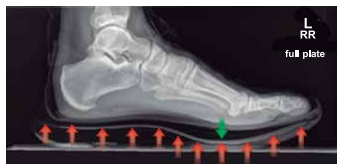

Observe a radiografia lateral do pé esquerdo de uma pessoa de 90 kg, usando um par de tênis com placa de carbono. As setas indicam o sentido da força quando a pessoa está em movimento, ou seja, correndo, quando apenas um de seus pés toca o solo.

Enunciado 4678238-1

Considere que a placa de carbono funcione como uma mola única e sofra uma deformação de 5 mm no instante em que a pessoa toca o solo, conforme o ilustrado. Ao admitir g = 10 m/s², a constante elástica da placa será, em kN/m, de